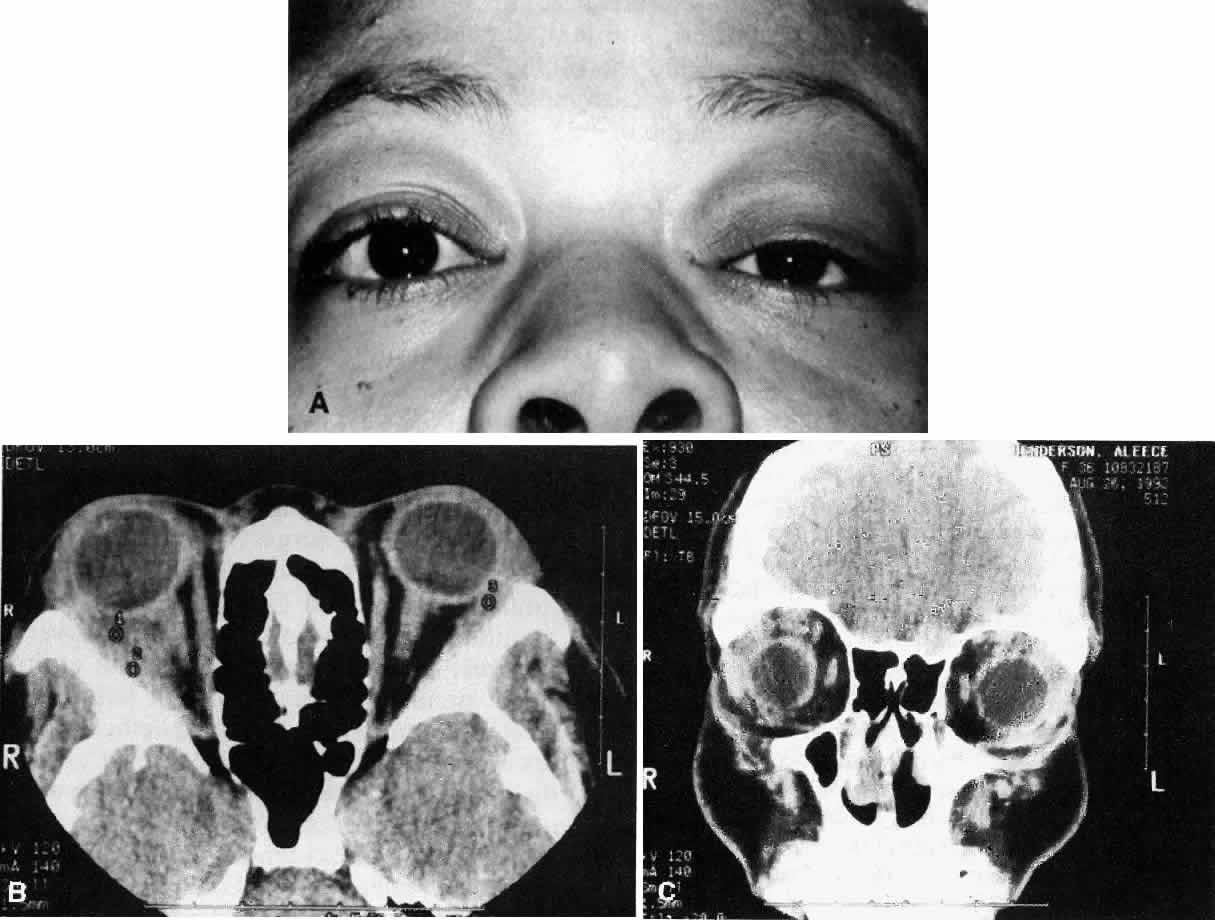

Fig. 1. A. A 36-year-old woman presented with right-sided pain and proptosis occurring over a several-day period. Externally the eye is quiet and does not appear inflamed. The patient had no complaints of diplopia or other visual disturbances. Tissue obtained at biopsy demonstrated idiopathic orbital inflammation. B. Axial CT image from the same patient demonstrates bilateral orbital masses located laterally in the orbits. Note that masses are ill defined and do not appear to have a capsule. The masses are molded to the bony orbital walls without evidence of any bony irregularities. C. Coronal CT image from the patient again shows the presence of bilateral orbital masses apparently involving the lateral rectus muscles.